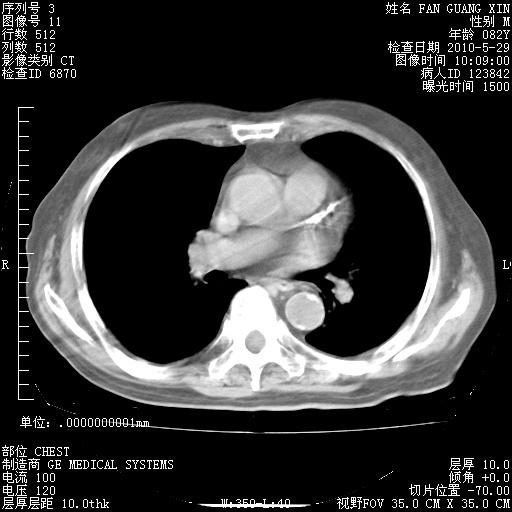

治疗3周后的肺部CT纵隔窗

再治疗10天后的肺部CT

再治疗10天后的肺部CT 纵膈窗

阅读此次胸部CT,肺间质渗出性改变较入院时有吸收。目前从体温、白细胞、中性分叶明显增高,肯定存在细菌感染(发生医院感染哦,若无消化道及泌尿系统等感染的依据,肺部感染可能大)。若你院头孢哌酮舒巴坦钠耐药率较高,同意你的方案,若48小时体温仍高,可考虑使用碳青霉稀类抗菌药物,同时可予超声雾化、注意滴数时加大液体量。白蛋白33.30g/L较低哦,需加强营养等支持治疗。